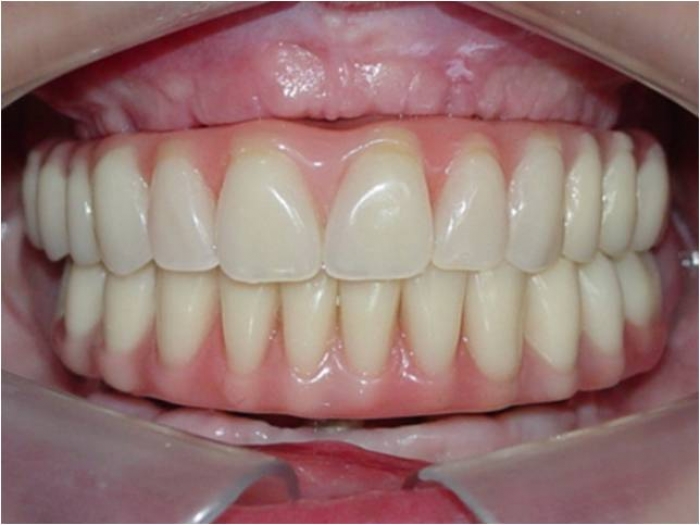

Sorriso final do caso terminado em outubro de 2012 - Clínica Cliniface

Sorriso final do caso terminado em outubro de 2012